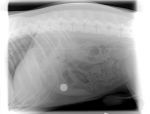

Xrays showed that he had swallowed a nice sized round fishing sinker (about 50 grams in weight).

Codys sinker (Medium).jpg